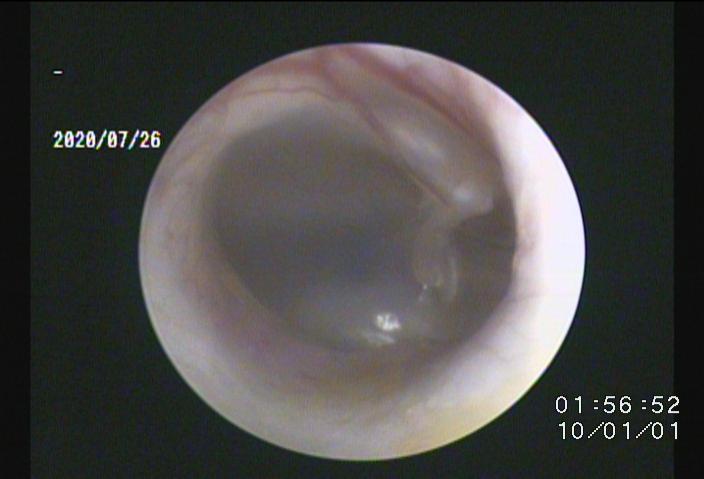

・当院では「耳道内視鏡」を導入し、今までは届かない部位で治療が困難であった鼓膜付近や中耳内、耳道壁の処置、徹底洗浄が可能です